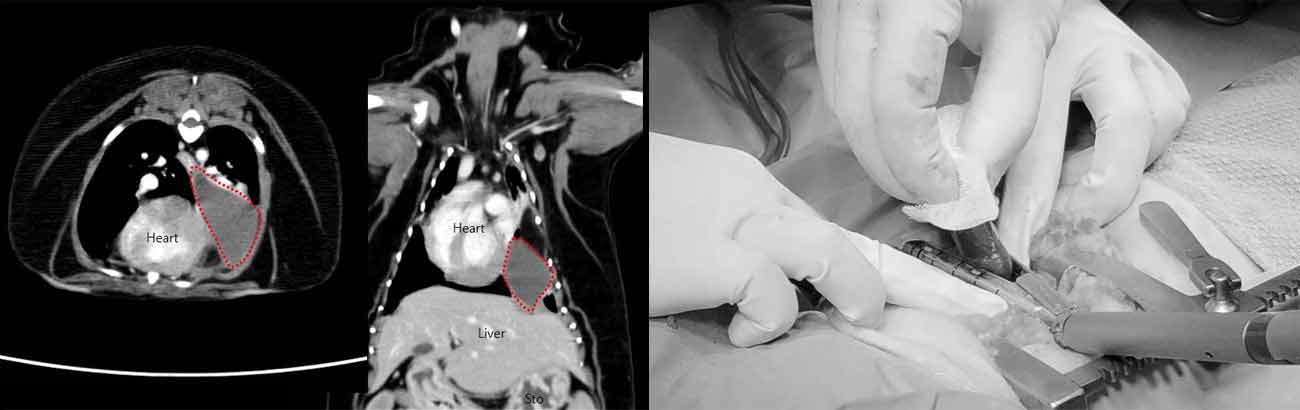

해마루 동물병원 수술센터는 2021년에 외과 수술실을 별관으로 확장 이전하여 보다 좋은 환경에서

분과별로 일반외과,

정형신경외과, 안과, 치과 분야에 최선을 다해 수술을 전문적으로 시행하고 있습니다.

고난도 수술을 위해 새로운 수술 및 진단 장비를 추가로 구비하였으며,

보다 멸균적인 수술 환경을 위해

넓은 면적의 멸균 수술실 2곳과 수술 준비실,

별도의 치과 수술실을 갖추게 되었습니다.

응급상황에서 정확하고 신속한 수술치료를 위해 본관에 응급 수술실을 별도로 운영하고 있습니다.